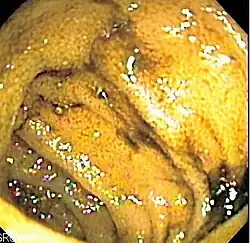

Die Doppelballon-Enteroskopie (DBE) ist eine endoskopische Untersuchungsmethode aus dem Gebiet der Gastroenterologie, mit der der Dünndarm untersucht werden kann.

Das Prinzip der Doppelballon-Enteroskopie besteht darin, den Dünndarm durch die Verwendung zweier Ballons an einem ca. 2 Meter langen Endoskop und einer darüber gestülpten Röhre (sog. Übertubus) aufzufädeln. Die DBE kann wie eine Magenspiegelung (Gastroskopie) über den Mund erfolgen (obere DBE) oder wie eine Darmspiegelung (Koloskopie) durch den Anus (untere DBE). Um den kompletten Dünndarm untersuchen zu können, muss meistens eine obere DBE und eine untere DBE miteinander kombiniert werden, meistens an zwei aufeinander folgenden Tagen. Dabei erfolgt dann eine Untersuchung der oberen Hälfte des Dünndarmes durch den oralen Zugangsweg, die untere Hälfte des Dünndarmes wird durch den analen Zugangsweg untersucht.

Im Rahmen der Untersuchung können Gewebeproben aus dem Dünndarm entnommen, Polypen abgetragen und z. B. blutende kleine Gefäßmissbildungen (Angiodysplasien) verödet werden (Argonplasmakoagulation).